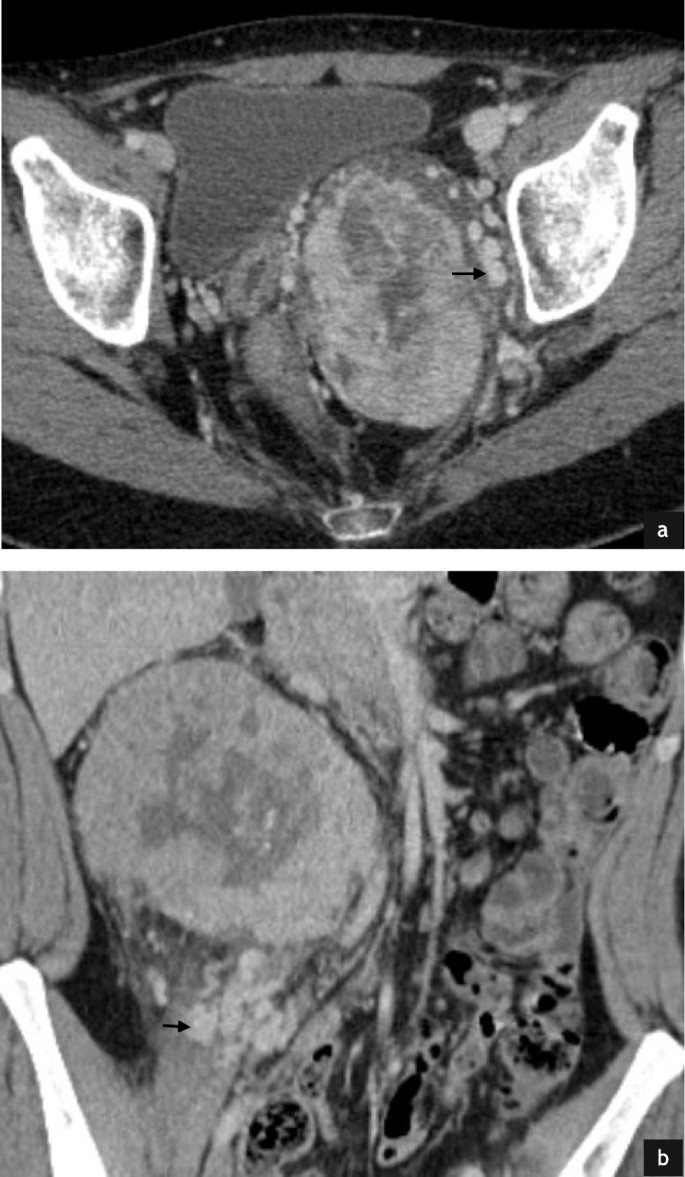

Intramuscular (4/ 32, 13%) and subcutaneous metastases (1/32, 3%) were also featured. Metastases in these locations were characterised by hypervascularity with demonstrable feeding vessels (Fig. 8). The pattern of distant bone metastases (5/32, 13%) in our cohort was varied with lytic, mixed lytic and sclerotic and sclerotic-only metastasis appreciated (Fig. 9). Soft tissue components were observed in 3/5 cases (60%).

Intramuscular and subcutaneous metastases from ASPS. Post contrast axial (a) and sagittal CT (b) in a 21 year old female with an intramuscular metastasis (a & b, white arrows) demonstrates a large feeding vessel (a & b, black arrows). Post contrast axial CT in this 28 year old female patient demonstrates markedly hyperenhancing subcutaneous metastasis (c white arrowhead) inferior to the xiphisternum. Again a small feeding vessel is appreciated (c, thick white arrow)

Bone metastases in two patients with alveolar soft part sarcoma. Axial CT of the pelvis on bone windows demonstrates multiple lytic metastases in this 69 year old male patient (a, black arrows). Coronal CT of the abdomen on bone windows in a 31 year old male patient demonstrates mixed sclerotic/lytic metastasis (b, white arrow) with associated with vertebral body collapse